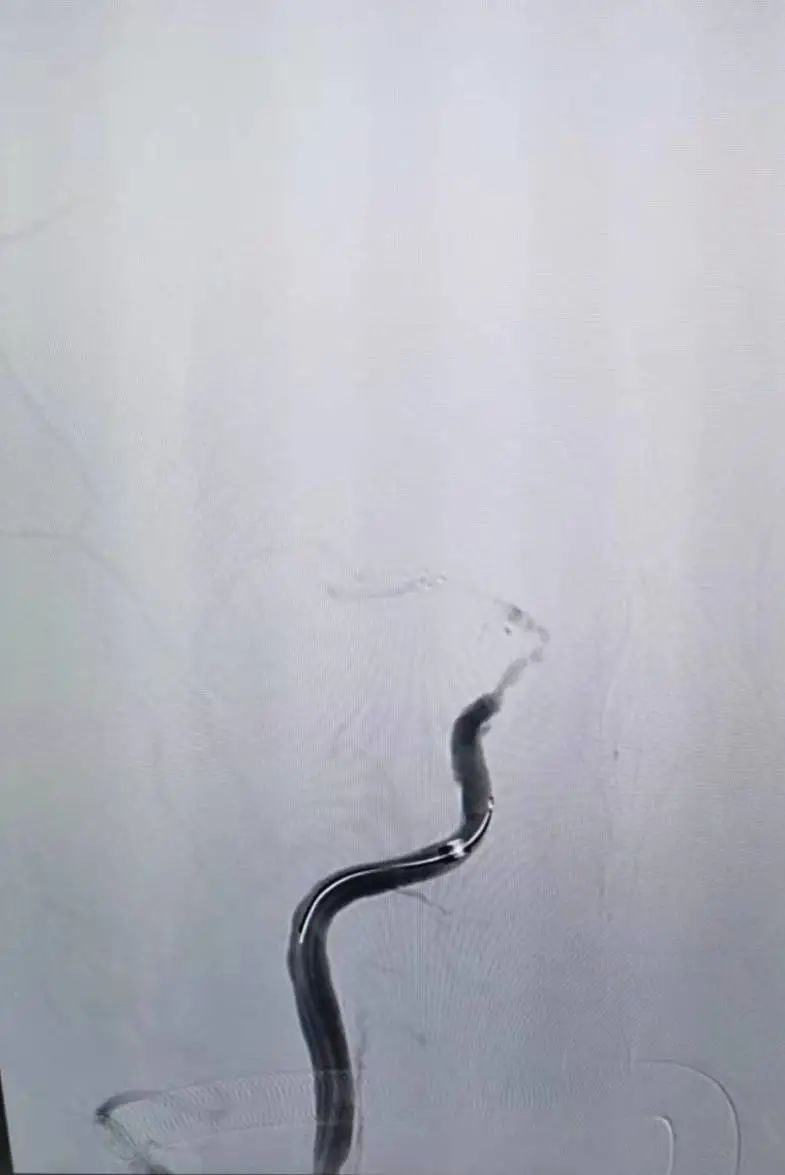

醫(yī)院立即開通卒中綠色通道,卒中團(tuán)隊(duì)在查閱患者CT后排除出血,建議立即進(jìn)行靜脈溶栓。因考慮顧奶奶為大血管閉塞,故與家屬溝通為顧奶奶進(jìn)行橋接治療。征得家屬同意后送入介入導(dǎo)管室,當(dāng)天晚上22:20開始行全腦血管造影,造影顯示顧奶奶左側(cè)大腦中動(dòng)脈上干閉塞,遂予左側(cè)大腦中動(dòng)脈取栓術(shù)。22:55,顧奶奶血管開通。術(shù)后顧奶奶被送入病房,右側(cè)肢體肌力明顯改善,從0級(jí)提升到3級(jí)。

圖丨溶栓+取栓

介入手術(shù)進(jìn)行中